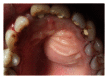

The aim of this case report is to present two cases where cone beam computed tomography (CBCT) was used for the diagnosis, treatment planning, and followup of large periapical lesions in relation to maxillary anterior teeth treated by endodontic surgery. Periapical disease may be detected sooner using CBCT, and their true size, extent, nature, and position can be assessed. It allows clinician to select the most relevant views of the area of interest resulting in improved detection of periapical lesions. CBCT scan may provide a better, more accurate, and faster method to differentially diagnose a solid (granuloma) from a fluid-filled lesion or cavity (cyst). In the present case report, endodontic treatment was performed for both the cases followed by endodontic surgery. Biopsy was done to establish the confirmatory histopathological diagnosis of the periapical lesions. Long-term assessment of the periapical healing following surgery was done in all the three dimensions using CBCT and was found to be more accurate than IOPA radiography. It was concluded that CBCT was a useful modality in making the diagnosis and treatment plan and assessing the outcome of endodontic surgery for large periapical lesions.